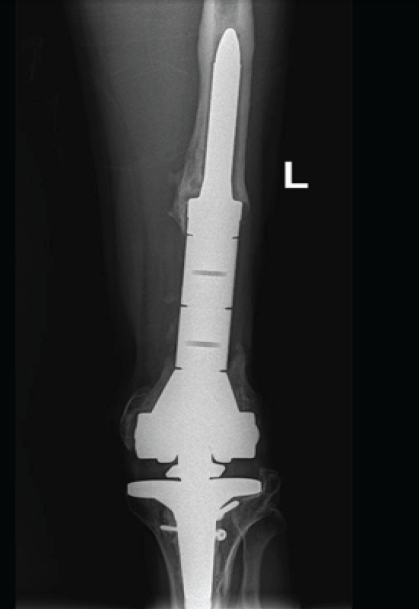

The case was discussed with orthopedic trauma surgeons and arthroplasty surgeons, along with the physiotherapy team, and a DFR followed by a structured physiotherapy plan was planned (Fig. 6).

Figure 6: Final post-operative radiographs showing distal femoral replacement.

For implantation, the final prostheses included a legacy posterior stabilized cemented femoral stem measuring 13.5 mm × 100 mm with an extra-small component, and a cemented tibial component measuring 150 mm × 12 mm with a tibial tray size 2. A polyethylene insert of size 14 was used (Fig. 6). After allowing the cement to cure, final assessment demonstrated a stable knee with full ROM. The quadriceps tendon was repaired, the arthrotomy was closed, and a drain was inserted. The subcutaneous tissues were closed in layers, and the skin was closed with skin clips. Sterile dressings were applied. The patient tolerated the procedure well and was transferred to the recovery room in good condition, with intact distal neurovascular status. He was planned for a few days of inpatient observation for pain control and to initiate full weight-bearing as tolerated. Discharge was planned once medically fit.